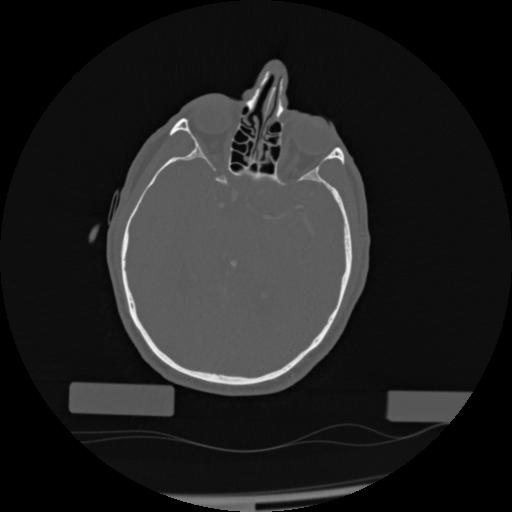

22 ANGIO,CE,Vol,0.5,ANGIO,,